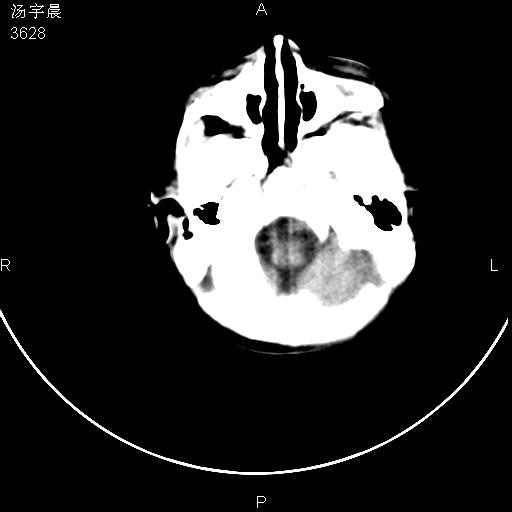

早产儿,现两月大,2月份在某医院诊断病毒性脑炎并治疗,mri报右颞部脑白质片状长t2信号,脑白质模糊。其他不详,现家属要求ct复查 。

双侧大脑半球大片状低密度,无明显占位表现, 符合病毒性脑炎。

小儿病毒性脑炎ct表现缺乏特异性,但其定位分布有一定特异性,单纯疱疹病毒性脑炎ct表现以颢叶病变为主,同时可累及其他脑区或伴出血,乙型脑炎表现为基底及丘脑的病变,流行性腮腺病毒性脑炎则ct表现可正常,故ct检查对病毒性脑炎的定性有重要的价值。 本例支持:病毒性脑炎的后遗改变!